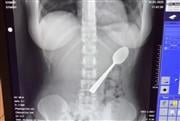

Πώς μια 28χρονη έφαγε κουτάλι των 17 εκατοστών αντί για γιαούρτι και τι συνέβη στο στομάχι της